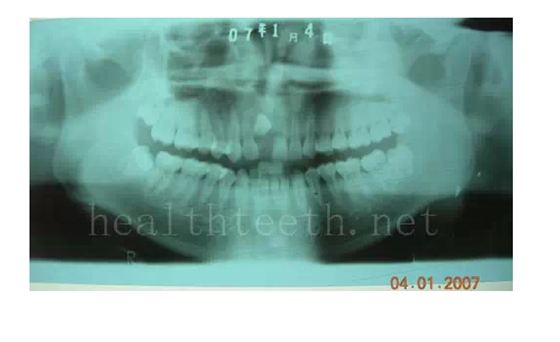

3、多生牙

病例1

QQ圖片20150722094304.png

QQ圖片20150722094321.png

病例2

QQ圖片20150722094347.png

QQ圖片20150722094402.png